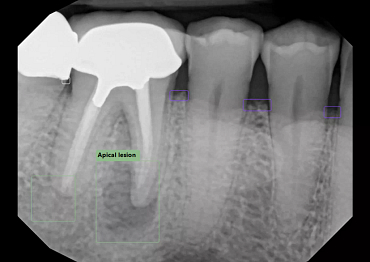

- Automatically file and organize radiographs

- Detect caries, calculus, bone loss, and other pathologies